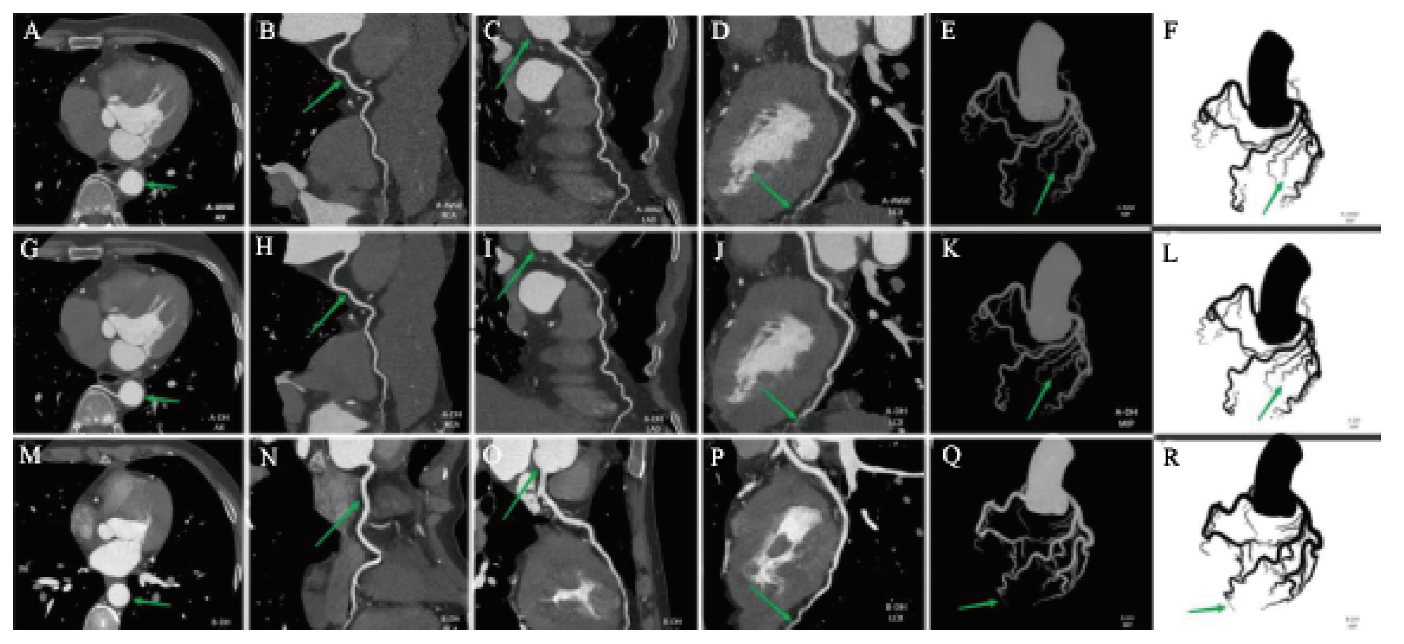

B-DLIR中AR、LAD、LCX、RCA的CT值均高于A-AV60及A-DLIR,比较差异均有统计学意义(P均< 0.001)。A-DLIR与B-DLIR相比,AR、LAD、LCX的噪声值相近,仅在RCA中比较差异有统计学意义(P < 0.05);A-DLIR与B-DLIR的SD均小于A-AV60,比较差异均有统计学意义(P均< 0.001)。A-DLIR与B-DLIR中AR、LAD、LCX、RCA的SNR、CNR相近,均高于A-AV60(P均< 0.05)。B-DLIR在客观图像评价中更具优势。见表3图2

图2 A-AV60、A-DLIR、B-DLIR 3种方案CCTA的原始轴位、CPR、MIP图

注:从左至右为原始轴位和RCA、LAC、LCX、MIP、MIP反转图。A~L是50岁男性患者的检查图,A~F采用A-AV60,G~L采用A-DLIR,包括冻结后的原始轴位、CPR和MIP。M~R是54岁女性患者的检查图,采用B-DLIR,包括冻结后的原始轴位、CPR和MIP。A、C、G、I、M、O箭头所指反馈了主动脉及主动脉根部管腔内噪点的评级,A、C噪声明显;B、H、N箭头所指反馈了冠状动脉的锐利度,B模糊、与脂肪边界欠清晰、锐利度评分最低;D、J、P箭头所指反馈了冠状动脉末端纹理伪影,D血管末端呈现塑料感、结节样伪影,连续性差;E、F、K、L、Q、R箭头所指反馈了末端纹理和小分支的可见度,E、F末端纹理伪影明显、小分支显示度最差。综合以上因素,5分评分法显示B-DLIR、A-DLIR评分高于A-AV60。

Figure 2 Original axial、CPR and MIP images of CCTA with three schemes: A-AV60, A-DLIR and B-DLIR